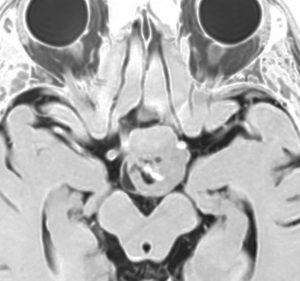

思春期の女の子にできた小脳腫瘍です。とても大きく見えますがほとんどが水たまり(のう胞といいます)。第4脳室が腫瘍で圧迫されて閉塞性水頭症になりました。のう胞の中に出血がありますが毛様細胞性星細胞腫では腫瘍内出血をしばしば見ます。右の写真で脳室が大きくなっています。こんなに大きいのに小脳症状は全くなくて,頭痛と嘔吐が症状でした。

赤で塗ったところだけが毛様細胞性星細胞腫です。これを取れば治ります。簡単な手術ですし後遺症も残りません。

手術後のMRIです。水頭症も改善してますから症状も消失しましたし,すぐに退院です o(^o^)o